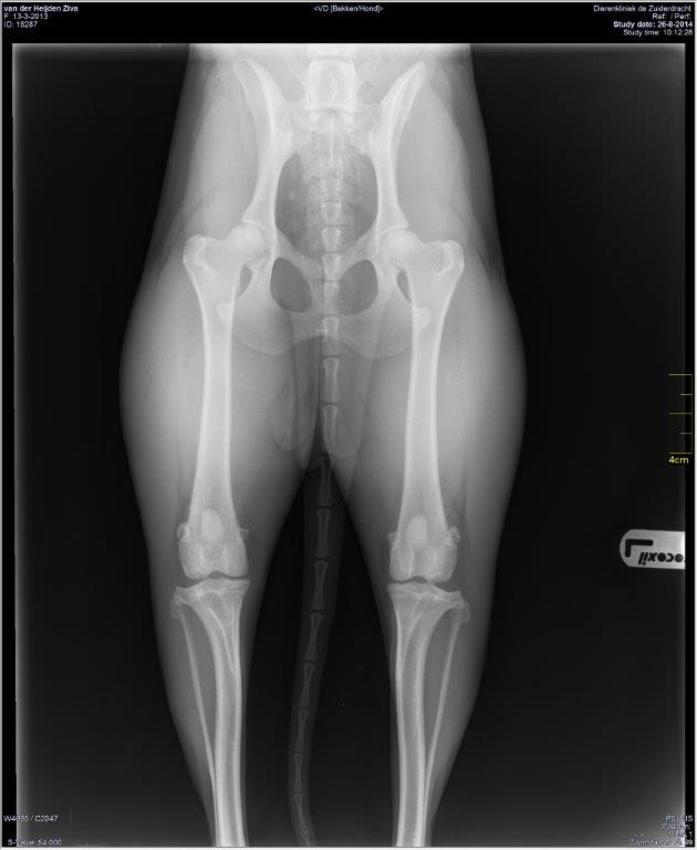

Dit is de foto van Ziva's heupen

omdat Ziva nog weleens met haar poot rechtsachter mankt, hebben we daar ook een foto van laten maken, maar helaas (en tegelijkertijd gelukkig) konden ze daar (opnieuw) niets op zien. Ze lijkt er gelukkig ook geen pijn aan te hebben.

Op het toestemmingsblad voor eventueel met sporten stond HD negatief, ik vroeg me af is dat hetzelfde als HDA?